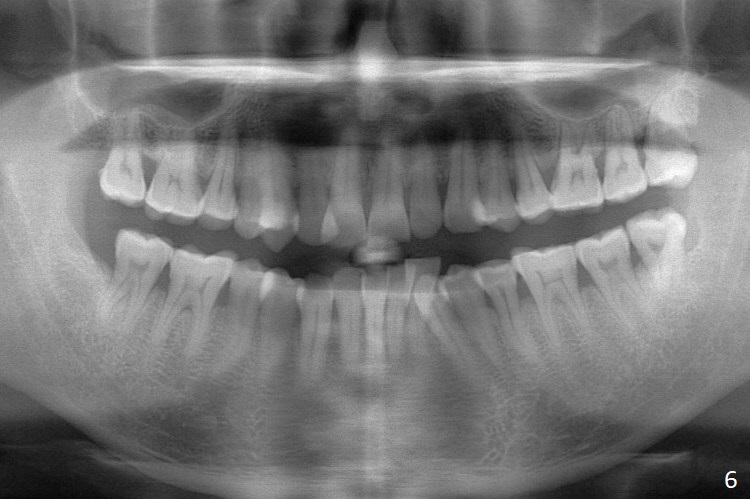

Enough Space For Crowding After Extraction? A 47-year-old man requests orthodontic treatment following SRP in other office (Fig.1-11). For severe crowding and midline shifting, extraction of four of the 1st bicuspids is imminent. Is it enough? To answer the question, model surgery is performed (Fig.12-16). 1st visit: periodontal maintenance, orthodontic consent (emphasizing oral hygiene) extract 4s and possibly L8s and separators. The beauty of this vist is that after local anesthesia and extraction including L8s, it is painless and easy to remove calculus from the proximal surfaces of the neighboring teeth. It is much easier to place separators after extraction. It is expected that there is no gingival erythema when the patient returns for bracketing. Take photos of UR3, similar to Fig.3. Molar banding is also anticipated to be easy with separator placement after extraction. Return to Ortho Cases Xin Wei, DDS, PhD, MS 1st edition 11/23/2017, last revision 04/28/2019